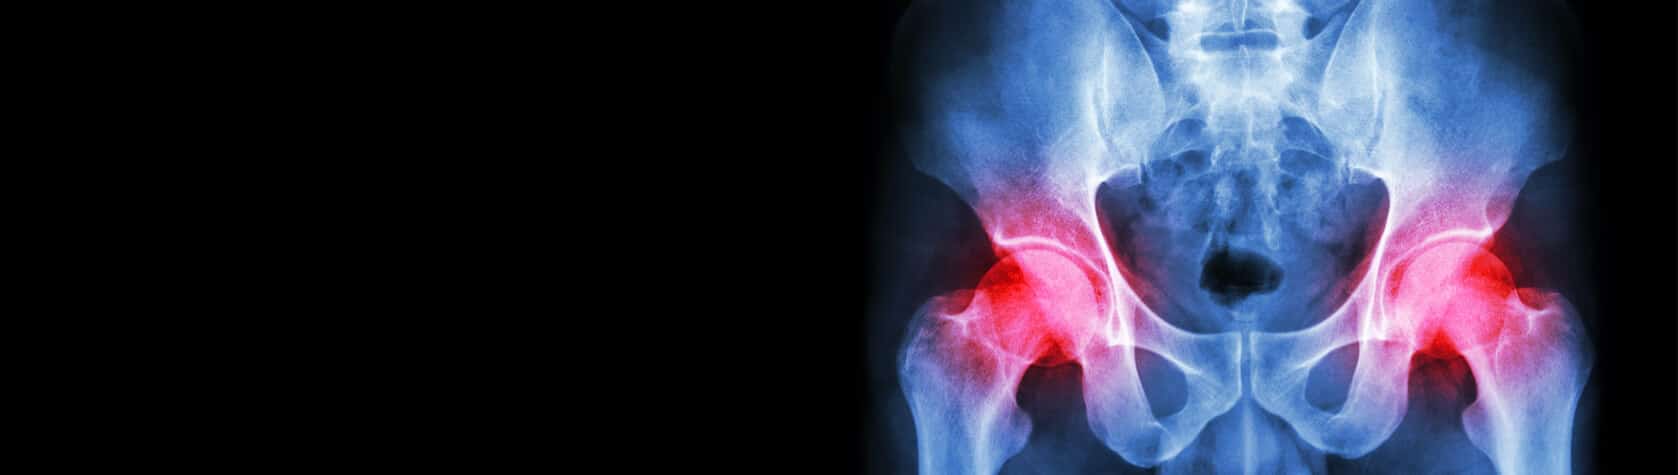

Expert Perspectives – Understanding Medical Malpractice With Total Hip Replacements

Medical malpractice claims for total hip replacements are rare but complex, often involving nerve injury, infection, or dislocation. Surgeon diligence and communication are key.

Total hip arthroplasty is widely regarded as one of the most successful orthopedic procedures in terms of patient satisfaction. Pain relief, improved functional independence, and better quality of life are almost always achieved. Nearly a half-million of these procedures are done annually in the United States alone; and the number is increasing steadily with the increased functional demands of our aging population. As with other surgeries, there are no “written down” standards for what is an acceptably well-done total hip arthroplasty and, as expected, the malpractice claim rate is very low. A study from the Netherlands looking at hip arthroplasty malpractice claims from 2000 to 2012, shows the incidence of a claim was less than 0.3 percent.